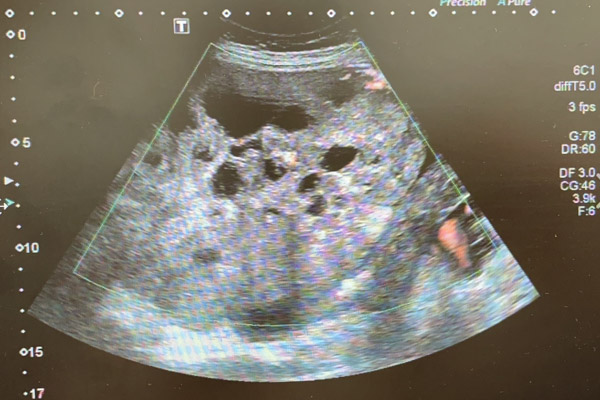

懷孕7個(gè)月的周女士孕期一直未建卡產(chǎn)檢,孕前也未做過體檢,幾周前,突然發(fā)覺腹部脹痛不適,到外院就診,經(jīng)超聲檢查后發(fā)現(xiàn)巨大盆腹腔包塊并已累及肝臟,了解病情后,為求母嬰平安,周女士于2021年11月1日到柳州市人民醫(yī)院產(chǎn)科進(jìn)一步住院診治。

為確保手術(shù)萬無一失,我院副院長(zhǎng)潘光棟博士、胃腸外科副負(fù)責(zé)人胡志立博士作為外科專家,在手術(shù)臺(tái)前與術(shù)者進(jìn)行了會(huì)診,并給予專業(yè)意見。手術(shù)過程中,進(jìn)行的每一步都如履薄冰,手術(shù)醫(yī)生憑借其精湛的技術(shù)以及對(duì)盆腔復(fù)雜解剖結(jié)構(gòu)的精準(zhǔn)把控,抽絲剝繭,一寸一寸推進(jìn),最終將重量達(dá)3530g,大小約20cm×15cm×10cm的巨大囊實(shí)性腫物取出體外,解除了這個(gè)時(shí)刻威脅著孕產(chǎn)婦及胎兒安全的“定時(shí)炸彈”,術(shù)后已轉(zhuǎn)重癥醫(yī)學(xué)科進(jìn)一步觀察治療。